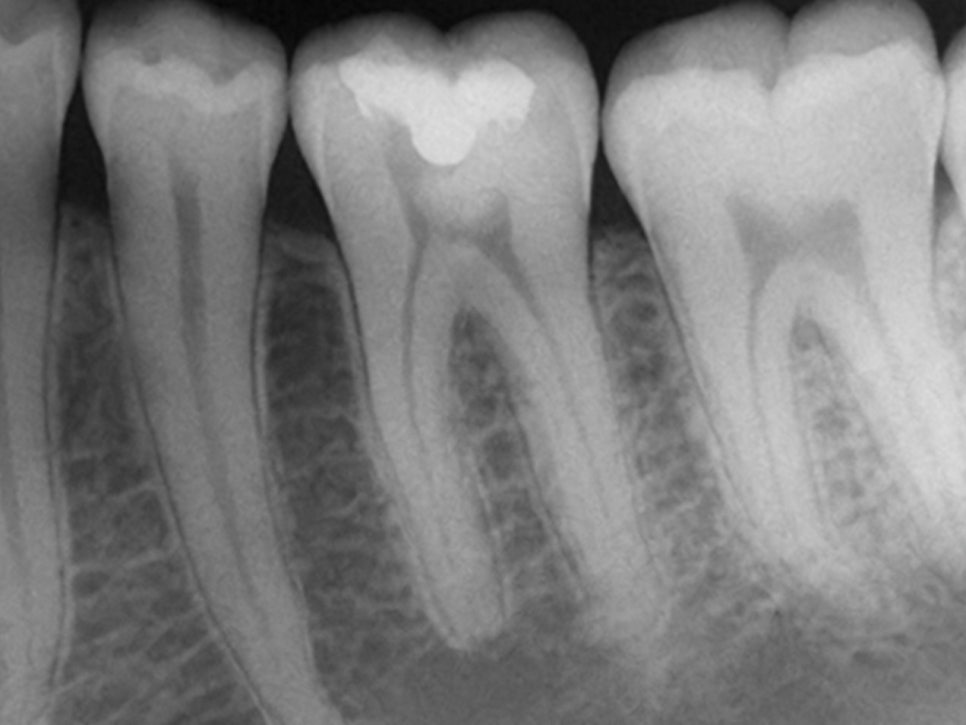

다만 이는 왜곡이 있을 수 있으므로

한 개의 치아를 자세히 보고 싶을 때는

작은 필름을 물고 2-3개의 치아만 찍어

해당 부위 및 주변 조직 상태를 알 수 있습니다.